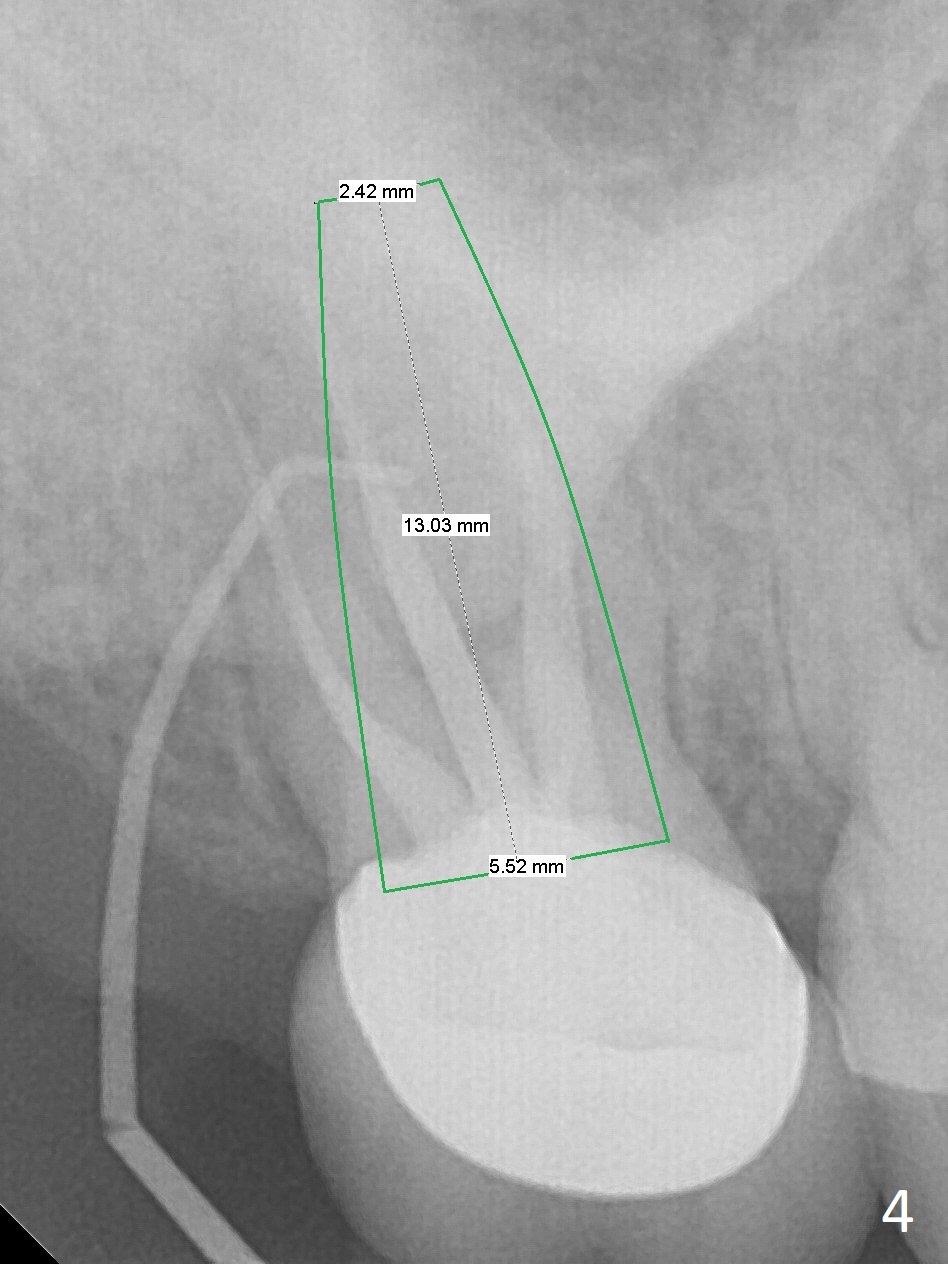

A 58-year-old woman has had RCT done at #2 for several years. The roots are trifurcated with sufficient bone height (Fig.1-3). Recently the tooth becomes symptomatic with formation of a distal fistula (Fig.4). After extraction, the septum (Fig.5 S) may be wide enough for initial drill (Fig.6). If not, resection the thin part of the septum (Fig.7 red line, with small or medium Rongeur) and use the initial drill (Fig.8). Anyway, take PA immediately to avoid sinus membrane perforation. If possible, adopt single drill technique.